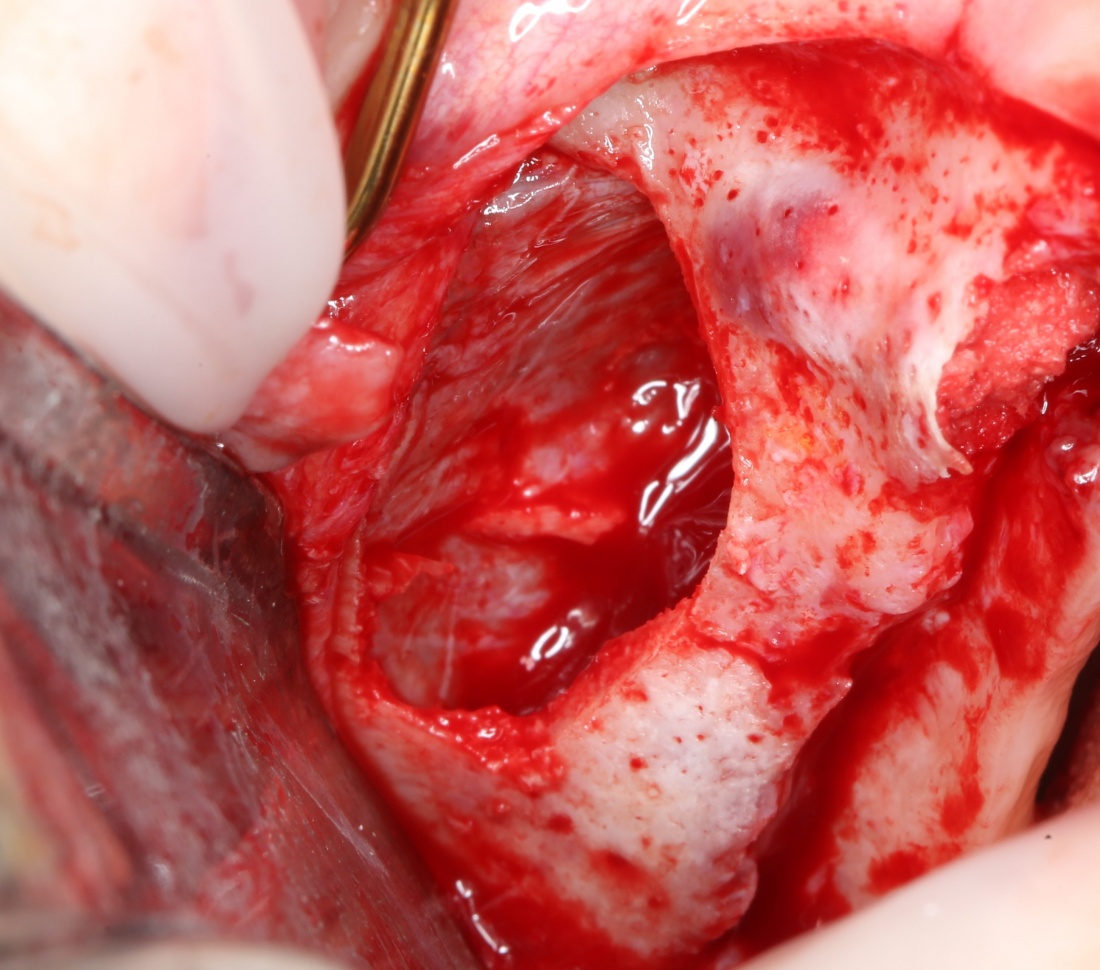

Синуслифтинг: что делать при перфорации слизистой оболочки гайморовой пазухи?